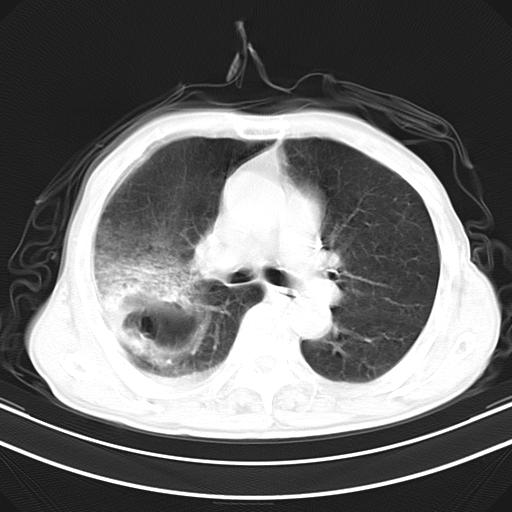

抗炎治疗10天后复查

抗炎治疗10天后复查:右上肺模糊阴影明显减少。